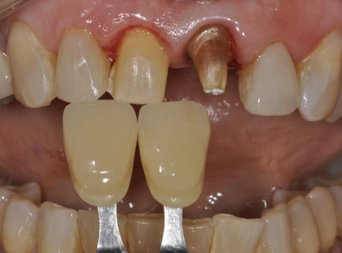

In this particular case, due to the different types of restorations to be fabricated, the correct shade selection is extremely important, as the final shade selection of the restoration must be made, as well as taking the shade of the dentin substrate. With the patient's help, shade A1 from the Vitapan Classical scale (Vita Zanhfabrik GmbH®) was chosen (Figure 7).

Figure 7 Choice of color A1 according to the Vitapan Classical scale (Vita Zanhfabrik GmbH®).

The shade selected for the dental substrate varied between A3.5 and A4 of the same scale. This information was sent to the laboratory in order to select the most appropriate ceramic material for the case (Figure 8).

Figure 8 Substrate color selected between A3.5 and A4 of the Vitapan Classical scale (Vita Zanhfabrik GmbH®).

To solve this case it was planned to fabricate two types of restorations, a ceramic veneer on tooth 11 and a full ceramic crown on tooth 21. Since these two types of restorations have different thicknesses (0.7 millimeters and 1.5 millimeters respectively), their aesthetic behavior would be different with respect to the final shade of the case, The infrastructure of the crown of tooth 21 would mimic the shape and color of the preparation for laminate present on tooth 11, thus allowing the two ceramic laminates, now with the same thickness, to be cemented with the same cementing agent, enabling a better uniformity of the final color (Figure 9).